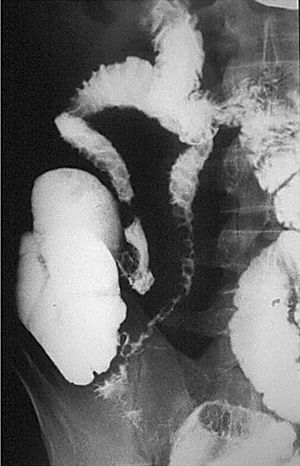

En la etapa inicial los hallazgos propios de la EII en el tránsito baritado son muy sutiles, tal vez discreto grado de espasmo con cierto grado de irritabilidad o alteración de la distensibilidad. De ahí que el estudio baritado tiene que ser realizado con una técnica exquisita, con sumo detalle, con compresión cuidadosa de cada una de las diferentes asas (fig. 3).

Fig. 3.--Enfermedad de Crohn, fase activa inflamatoria. (A) Discreto enderezamiento, rectificación y engrosamiento de pliegues intestinales a nivel de las asas yeyunales. (B) La correlación de tomografía computarizada (TC) muestra la hiperemia y la estratificación tan propias de la situación inflamatoria activa de la pared intestinal.

En la fase activa hay presencia de úlceras superficiales o aftoides (fig. 4). Pueden evolucionar haciéndose ulceraciones fisurantes longitudinales y transversales, dejando entre sí islotes de mucosa normal, constituyendo el concepto de patrón en "empedrado" (fig. 5).

Fig. 4.--Enfermedad de Crohn, fase activa inflamatoria. (A) En el estudio baritado, a nivel de íleon distal se observan pequeñas imágenes puntiformes de cúmulo de bario rodeadas de un halo de edema, que corresponden a úlceras superficiales o aftoides. (B) Correlación endoscópica.